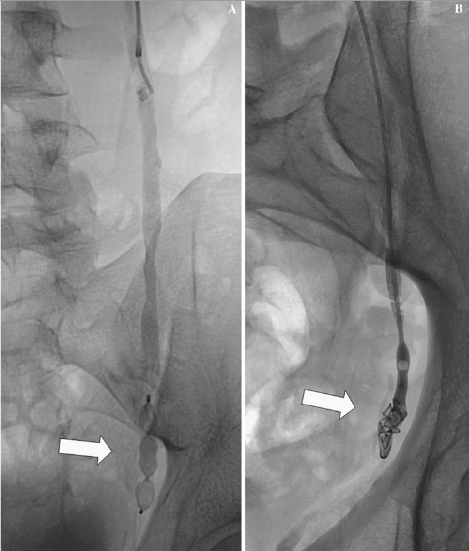

Varicocele Embolization

A Variocele is an enlarged vein in a male's scrotum with abnormal blood flow that may cause pain, swelling or infirtility. Varicocele embolixation uses imaging guidance and catheter (long, thin, hollow, plastic tube) to place tiny coils and/or a liquid substance in a blood vessel to divert blood flow away from a varicocele. It is less invasive than conventional surgery,can safely relieve pain and swelling, and may improve sperm quality.